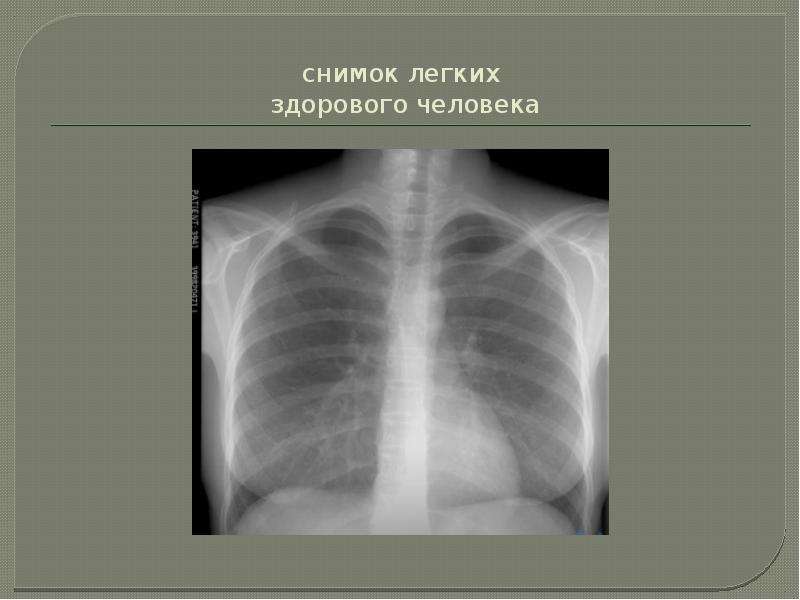

Рентген здоровых легких: примеры снимков и советы